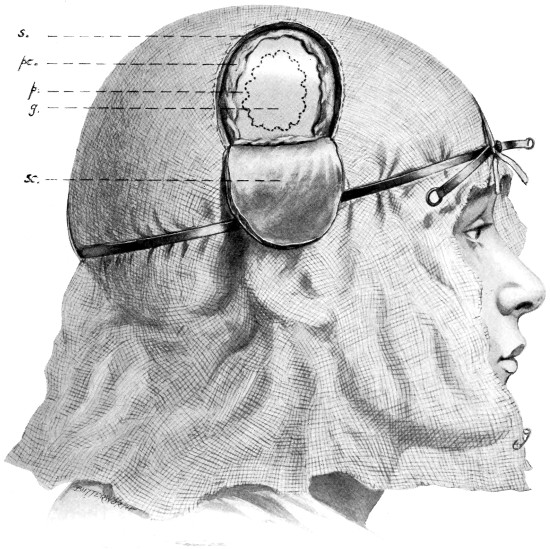

Fig. 4. The Scalp-tourniquet. Front View.

Fig. 5. The Scalp-tourniquet. Back View.

All surgeons must have appreciated the difficulty attendant on the application of forceps to, and the ligature of, divided scalp-vessels. The patient may lose a considerable quantity of blood, and much valuable time will be wasted before the more essential part of the operation is commenced. All this can, under ordinary circumstances, be avoided by the use of the scalp-tourniquet. As used by Cushing it consists of a rubber ring fashioned after the style of an Esmarch’s tourniquet, encircling the head and passing from the lower frontal region in front, above the ears, to the lower occipital region behind. A median tape, passing from glabella to occiput, prevents any tendency for the tourniquet to slip down over the eyes, at the same time acting as a convenient landmark for the superior longitudinal sinus.

The tourniquet, when applied with the correct pressure, should, under ordinary circumstances, completely control all hæmorrhage from the divided scalp-vessels. It should be noted, however, that[14] bleeding will be rather increased than otherwise if the tourniquet be so loosely applied as to impede the venous return without compressing the scalp arteries. A little experience will soon enable the operator to gauge the requisite pressure.

I found Cushing’s tourniquet rather inconvenient in its application, and, after various modifications, am accustomed to use the one depicted in the illustration. It consists of two flat metal bands connected posteriorly by a strong rubber connecting link, the two bands passing in front through a metal fixation piece possessing a screw which, when tightened up, allows of the maintenance of the desired pressure. The median tape, previously mentioned, helps to keep the tourniquet in position.

The tourniquet is applied as follows: the whole head is enveloped in gauze—two or three layers thick, and cut to the size and shape of a large handkerchief. The tourniquet is slipped over the head,[16] as low down as possible, and then tightened up. The median tape, having a loop behind through which the tourniquet passes, is laid in the middle line and tied round the screw on the fixation piece.